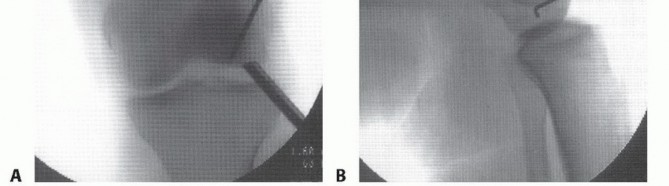

Avascular Necrosis

In AVN, plain films evaluate for evidence of collapse and secondary arthrosis (

FIG 9

). Once present, core decompression is not indicated.

MRI aids in determining the location and extent of subchondral bone involvement. Only lesions extending to subchondral bone are at risk for collapse and, therefore, appropriate for core decompression.

FIG 9 • A,B. AP and lateral radiographs demonstrating collapse of the tibial surface in AVN. (Reprinted with permission from Diduch DR, Hampton BJ. Avascular necrosis drilling in the knee. In: Miller MD, Cole BJ, eds. Textbook of Arthroscopy. Philadelphia: Elsevier, 2004:593-599.)